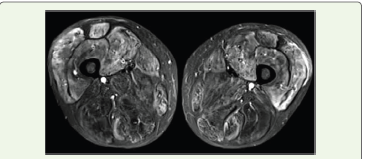

and Myonecrosis was confirmed via MRI. Bone marrow aspiration

showed lymphoplasmatic cells and plasma cells constituting 20% of

all Mononuclear cells.

Early suspicion and prompt antibiotic initiation is crucial to reducesubsequent mortality and morbidity. We established Myonecrosis due the presence of heterogenous muscle density on USG limb which was then followed by MRI of the affected parts, an elevated CPK enzyme and resolution of infection as per empirical antibiotic initiation on meropenem, vancomycin and clindamycin. The LRINEC score is commonly used to differentiate NSTI from other soft-tissue infection scan help clinical decision between a conservative management (likeourcase) vs a surgical one. However, this core poses a challenge in neutropenic patients as in those that might been countered in MM/WM. While radiological evidence can suggest NSTI a strong clinical suspicion is required for early diagnosis in the disease course [20-22]. Notably, NSTI has also been reported with the treatment of Lenalidomidein MM in the past [19].